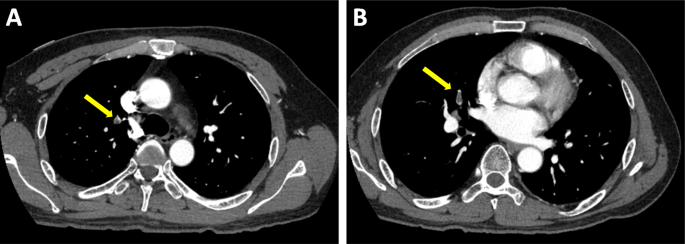

A 49-year-old Japanese man had splenic infarction with unknown cause 2 years ago. He had continued to take warfarin as anticoagulant therapy, but stopped taking the medication as self-judgment several months ago. He had no classical arteriosclerosis factors (hypertension, dyslipidemia, diabetes mellitus, and smoking status). He had sudden-onset rest chest dorsalgia and was transported to our hospital. Immediately after arrival, his pain temporarily improved. On initial examination, his blood pressure was 130/83 mmHg, pulse rate 110 beats/min, respiratory rate 30 cycles/min, and oxygen saturation 100% on room air. His physical examination showed a regular heart rhythm and no murmur, normal respiratory sounds in both lungs, and no edema in his lower extremities. On initial laboratory test, his high-sensitivity troponin I level was 1453.1 pg/mL (normal range: 0.0–26.2), creatinine kinase (CK) 261 U/L (59–248), CK-MB 26 U/L (0–6), platelets 31.5 × 104 /μL (15.8–34.8 × 104), fibrinogen 237 mg/dL (190–390), and D-dimer 1.7 μg/ml (0–0.9). Initial electrocardiography showed normal sinus rhythm and no ST-T change. Transthoracic echocardiography revealed normal wall motion and no asynergy. Contrast computed tomography (CT) showed a small PE and no aortic dissection (Fig. 1a, b). However, he complained of chest pain again following CT. Emergent coronary angiography (CAG) showed no severe stenosis in the right coronary artery and left circumflex artery, but a large thrombus with Thrombolysis In Myocardial Infarction (TIMI) grade 3 flow from the proximal to mid portion of the left anterior descending (LAD) artery (Fig. 2a-c). A 7-Fr guiding catheter was advanced through the left radial artery to the left coronary artery ostium, and a guidewire was advanced to the distal LAD artery. Near-infrared spectroscopy–intravascular ultrasonography (NIRS–IVUS) showed a large amount of thrombus from the proximal to the mid LAD artery, and the max lipid core burden index (LCBI) was 81 (Fig. 2d). Thrombectomy was performed using a 7-Fr aspiration catheter (Fig. 3a) and intracoronary thrombolysis by urokinase 60,000 U. Angiography and NIRS–IVUS revealed decreased thrombus in the LAD artery (Fig. 3b-c). The procedure was completed at this time because additional angioplasty with or without stent was at high risk of slow-flow phenomenon. In the pathological findings, the collected thrombus using an aspiration catheter had many fibrin precipitates. We suspected paradoxical embolism because the ultrasonography revealed a DVT in the bilateral lower leg, but contrast CT and transesophageal echocardiography showed no right-to-left short circuit including a patent foramen ovale, atrial septal defect, and ventricular septal defect, and pulmonary arteriovenous fistula. Further examination of coagulation abnormality revealed hyperhomocysteinemia (total homocysteine level: 140.8 nmol/mL [6.3–18.9], vitamin B12: 121 pg/mL [180–914], folate: 2.3 ng/mL [> 4.0], protein C activity: 111% [70–140], and free protein S: 131.7% [60–150]). Therefore, he was diagnosed with ACS complicated with PE and DVT simultaneously induced by hyperhomocysteinemia. He continued antithrombotic therapy using aspirin, warfarin (his international normalized ratio was controlled from 2 to 3), and heparin (1.5–2.5 times the reference value activated partial thromboplastin time) for 1 week. Peak CK was 347 U/L, and NIRS–IVUS and optical coherence tomography (OCT) revealed decreased thrombus and no significant residual organic stenosis in the LAD artery following 1 week of antithrombotic therapy (Fig. 4a). He was discharged from our hospital continuing antithrombotic therapy with aspirin and warfarin. Follow-up CAG and OCT after 9 months revealed complete thrombus disappearance in the LAD artery (Fig. 5a). His total homocysteine level had decreased to 85.1 nmol/mL by the dietary therapy. He had no cardiovascular event or major bleeding for 1 year.

Baseline coronary angiography and near-infrared spectroscopy–intravascular ultrasonography. Coronary angiography (CAG) revealed severe stenosis from mid to proximal left anterior descending (LAD) artery and no severe stenosis in the right coronary artery and circumflex artery (A-C). Near-infrared spectroscopy–intravascular ultrasonography (NIRS–IVUS) findings in the culprit lesion showed a low echoic component suspecting thrombus continuing from mid to proximal LAD (D-a, b, c) and organic fibrous plaque behind the thrombus. The lipid plaque is shown as a yellow region on the chemogram. NIRS chemogram map presented the maximal lipid core burden index (4 mm) = 81 (D-d)